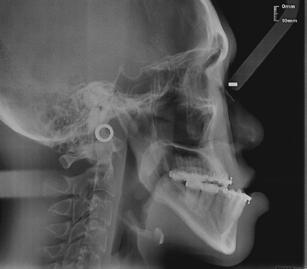

X-rays showing jaw misalignment and correction before and after orthognathic surgery respectively.

One bite at a time

When it comes to straightening crooked teeth, dental braces or retainers are the first go-to solution. However, for people with severe misalignment in their jaws, a more major intervention — such as orthognathic surgery — may be required.

Orthognathic surgery, also known as corrective jaw surgery, aims to correct deformities or misalignment of the upper and lower jaws. These deformities and misalignments can result in malocclusions, which refer to conditions where the upper and lower teeth are misaligned when the mouth is closed — common forms include underbites, overbites or open bites.

Orthognathic surgery can also address other conditions, such as facial injuries and severe obstructive sleep apnea (OSA). In cases of severe OSA, misaligned jaws can restrict the airway, leading to breathing difficulties. Surgery to reposition the jaws and widen the airway can ease breathing problems and alleviate OSA.

A multi-stage treatment process

Rather than a single procedure, orthognathic surgery is a comprehensive course of treatments combining both orthodontic and surgical approaches that can take years to complete. As orthognathic surgery is a major intervention, it is usually prescribed when patients experience difficulties in functional issues, such as chewing, biting or speaking properly.

According to Dr Leonardo Saigo, Consultant and Deputy Head, Department of Oral and Maxillofacial Surgery, National Dental Centre Singapore, patients who undergo orthognathic surgery typically

“At times, a surgery-first approach, where patients undergo orthognathic surgery without pre-operative orthodontic treatment, is possible,” said Dr Saigo. “This will reduce the treatment time significantly. However, the orthodontist and surgeon must assess if a patient is suitable for surgery first.”

Assessing suitability for surgery

While there is no age limit for orthognathic surgery, the treatment process for younger patients with underbites, overbites and open bites typically starts only after their period of growth has concluded. “Some patients who present early may be suitable for interceptive orthodontic treatment in the hope of avoiding the need for orthognathic surgery. However, it may not always be successful,” said Dr Saigo. “Most patients come in for treatment after their completion of growth as it will ensure post-surgical stability and lower risk of relapse.”

According to Dr Saigo, underbites have a higher incidence among Asians, affecting approximately 20 per cent of the population. If left untreated, severe underbites can lead

after

to ongoing biting issues or wearing out of teeth towards the back of the mouth at a faster rate. “Some patients may complain of difficulty articulating certain words due to the gap between the front teeth. Additionally, having a longer lower jaw may affect their self-esteem and confidence regarding their appearance,” said Dr Saigo. “We have had young patients who initially declined surgery due to various reasons, only to return for orthognathic surgery after a number of years, having realised that the condition actually has a direct and significant impact on their quality of life.”

The jaw correction process goes beyond a single operation, often involving both orthodontic and surgical treatments over years.

before